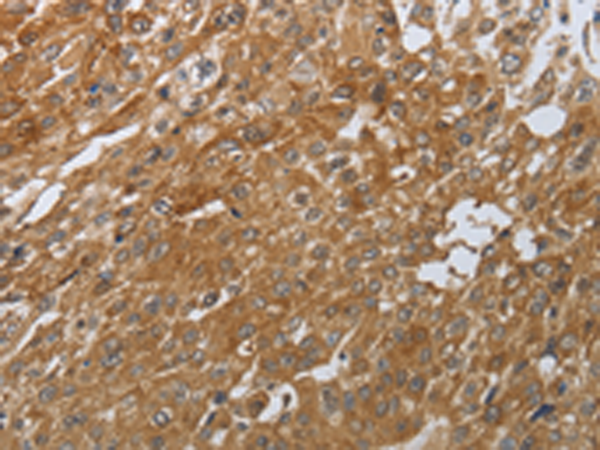

分类: 科研抗体货号: P11294别名: NSBP1, NBP-45应用: IHC反应种属: Human